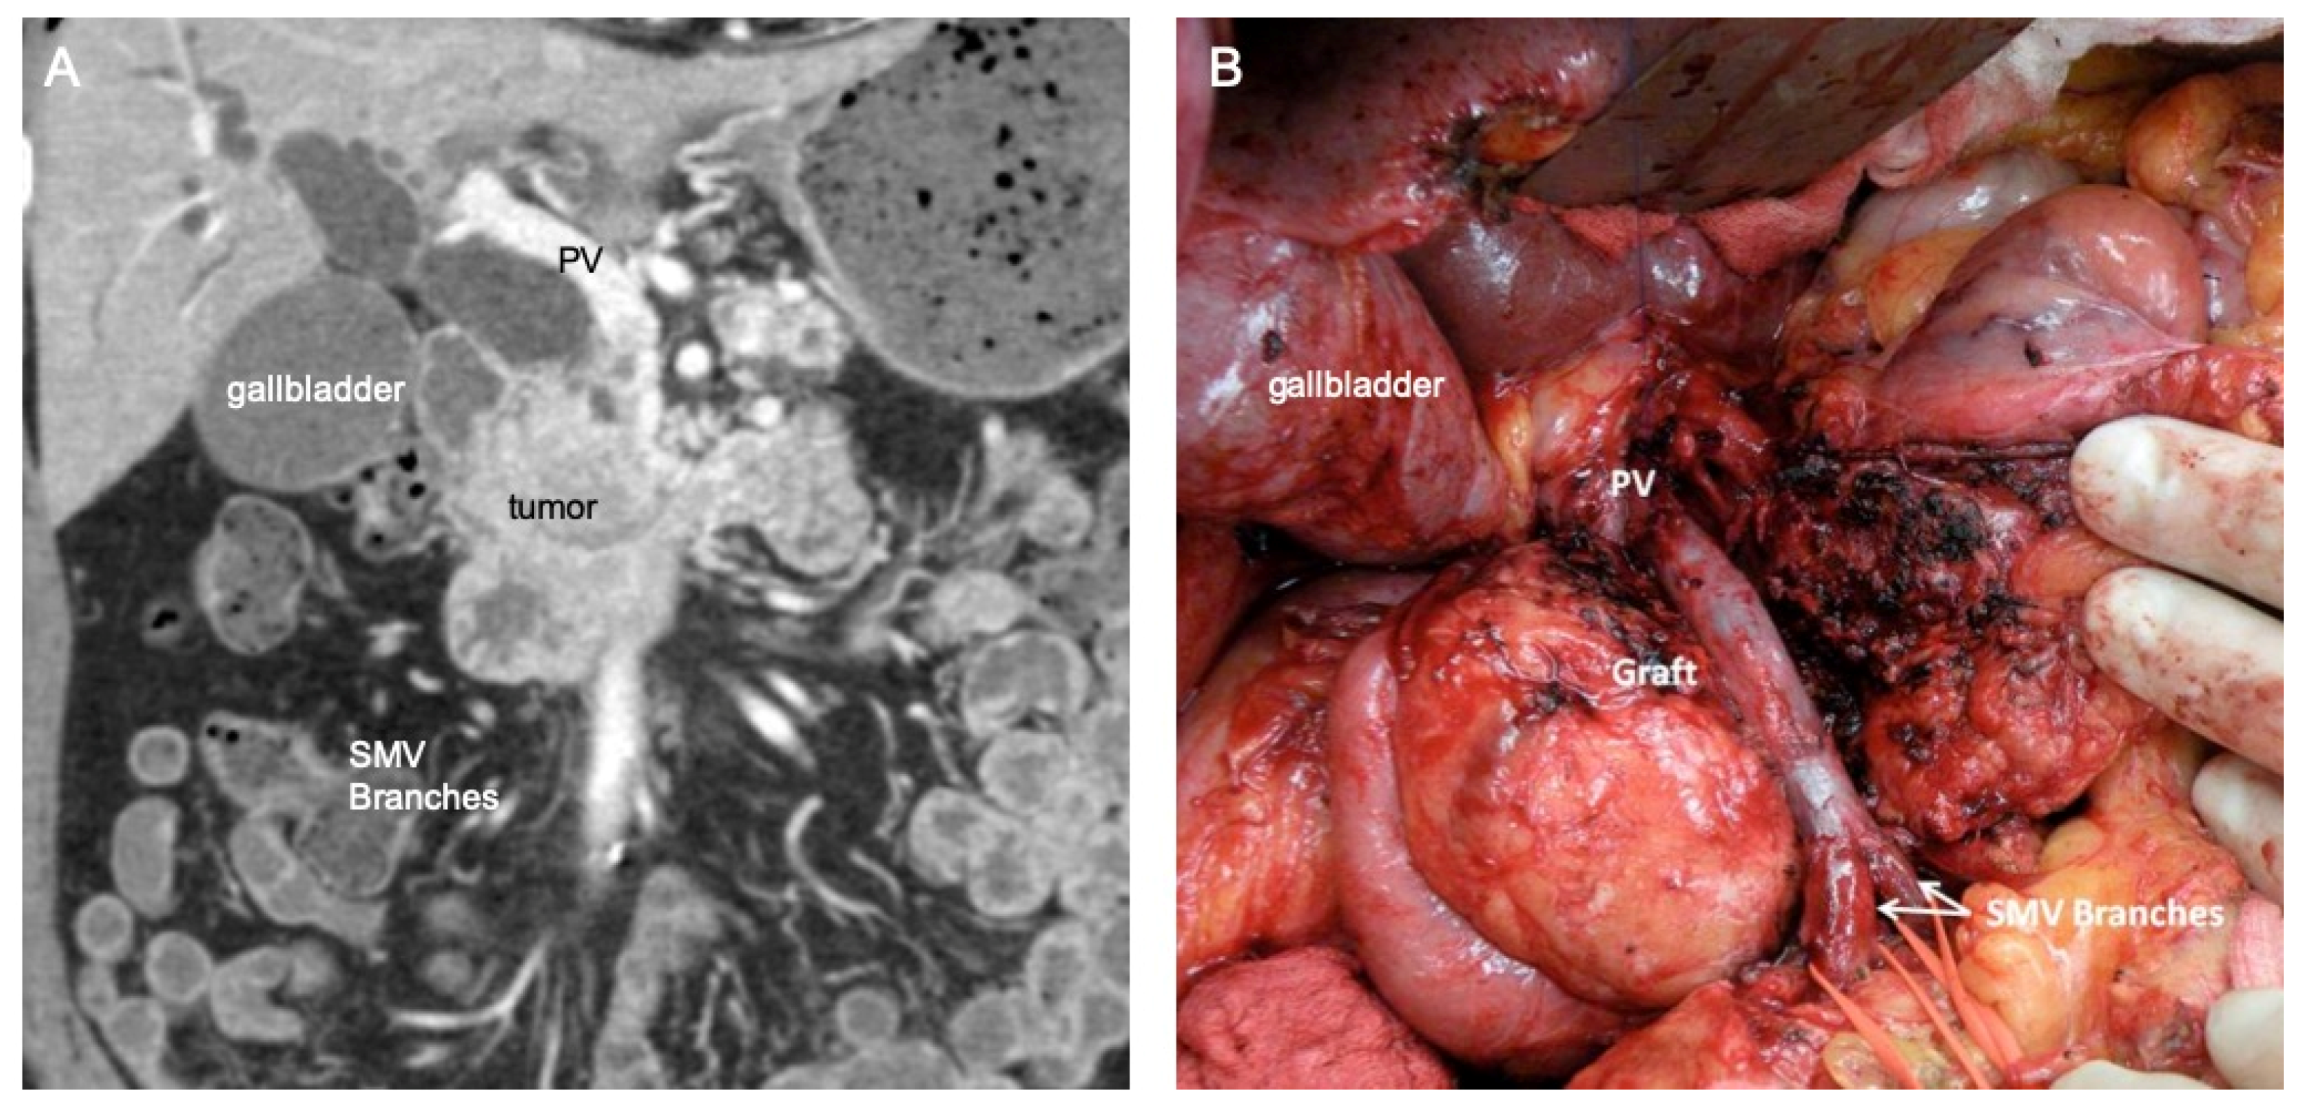

3.2. Traditional Vein Reconstruction